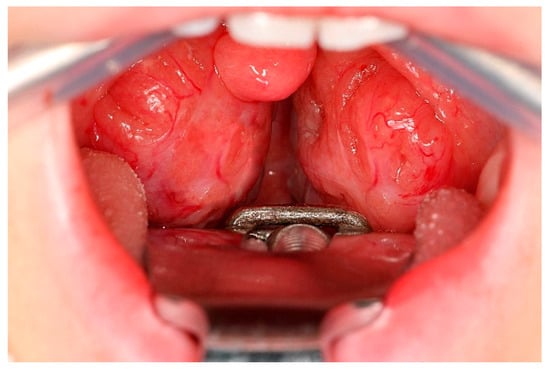

Effects of Web-Based Orofacial Myofunctional Therapy on Hyoid Bone Position in Adults with Mild to Moderate Obstructive Sleep Apnea: Evidence from an Estonian Substudy of a Randomized Controlled Trial

Background: Orofacial myofunctional therapy (OMT) is an emerging adjunctive treatment for obstructive sleep apnea (OSA), but its effects on upper airway structural support, particularly the hyoid complex, are not well defined. This study assessed the short-term effects of OMT on hyoid bone [...] Read more.

Background: Orofacial myofunctional therapy (OMT) is an emerging adjunctive treatment for obstructive sleep apnea (OSA), but its effects on upper airway structural support, particularly the hyoid complex, are not well defined. This study assessed the short-term effects of OMT on hyoid bone position and sleep-related indices in adults with mild to moderate OSA. Methods: In this assessor-blinded randomized controlled trial (ClinicalTrials.gov Identifier: NCT06079073), 13 adults with mild to moderate OSA were randomized to a 12-week web-based OMT program (n = 9) or a waitlist control group (n = 4). Cone-beam computed tomography (CBCT) and three-night home sleep testing were performed at baseline and follow-up. The primary outcome was change in axis-based cephalometric hyoid position measures; secondary outcomes included sleep parameters such as the apnea–hypopnea index (AHI). Results: No significant within- or between-group differences were observed in AHI, oxygen desaturation index, or mean nocturnal SpO2 after 12 weeks (all p > 0.05). However, several cephalometric variables showed significant between-group differences. The waitlist group exhibited greater posterior–inferior hyoid displacement than the OMT group, with large effect sizes across multiple vector measures (all p ≤ 0.045; r = 0.56–0.66). Posterior and inferior hyoid displacement was associated with higher AHI and lower SpO2, whereas increased lower pharyngeal airway width was associated with lower AHI. Conclusions: Short-term OMT did not improve sleep-disordered breathing indices but was associated with stabilization of hyoid bone position. These findings suggest that structural stabilization may precede functional improvement and highlight the clinical relevance of vector-based hyoid analysis. Full article